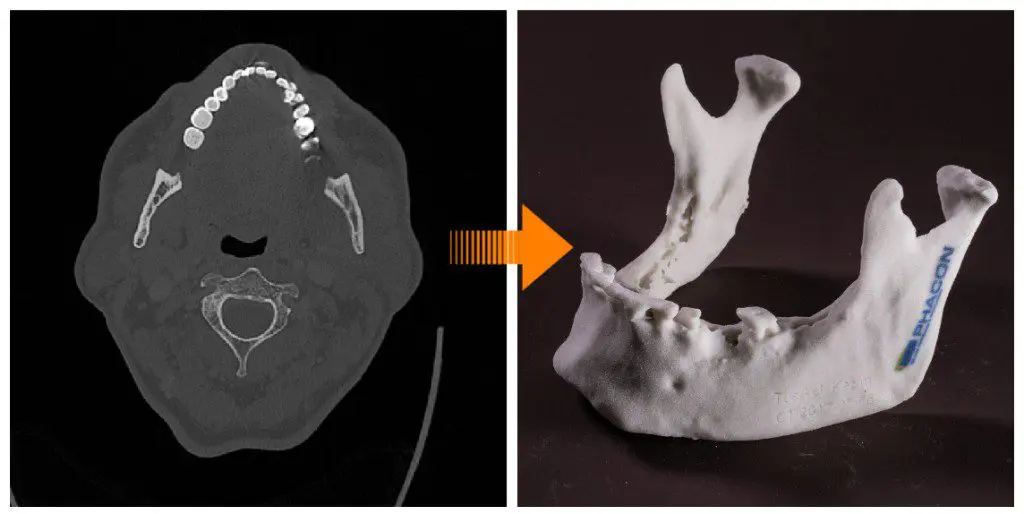

Darüber hinaus hat PHACON eine spezielle Methode entwickelt, die Ihnen die Operationsvorbereitung signifikant erleichtert.

Basierend auf medizinischen Bilddaten (CT, MRT, segmentierte Daten) erstellen wir für Sie patientenspezifische 3D-Modelle. Sie werden aus verschiedenen Materialien bis ins kleinste Detail von Hand gefertigt. PHACON-Patienten sind individuelle 3D-Modelle, die auf realen Daten basieren und eine Vielzahl menschlicher Gewebemerkmale (Knochen, Knorpel, Muskeln, Haut und Nerven) enthalten. Sie wurden entwickelt, um eine Vielzahl von Operationen mit austauschbaren und kompatiblen PHACON Patienten unterschiedlicher Anatomie zu simulieren. Die PHACON Patienten sind außerdem mit verschiedenen Trackern ausgestattet, die eine präzise Navigation der chirurgischen Instrumente ermöglichen, um Verletzungen zu erkennen. Genau wie im OP.